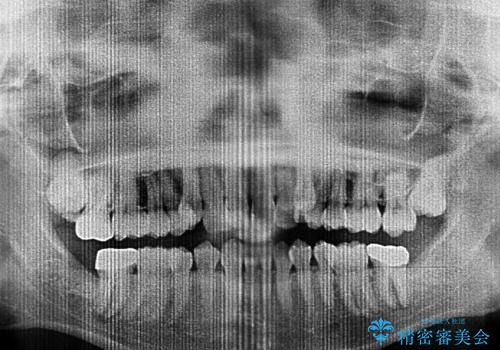

上顎の八重歯と下顎前歯の欠損 ワイヤー装置による抜歯矯正

- 上顎の八重歯を気にして来院された患者様です。

診察したところ、下顎前歯が2本欠損していたため、上下のバランスを取りながら八重歯を改善するため、上顎左右第一小臼歯2本を抜歯することとしました。

下顎左右大臼歯の歯根部に病変があったため、矯正治療前に根管治療を行い、矯正治療後にセラミッククラウンによる補綴治療を行うこととしました。

下顎前歯と本来抜歯矯正で抜歯する歯とは大きさが異なるため、仕上がりの咬み合わせは理想的なものとはなりませんでしたが、気になっていた八重歯はきれいに改善することができました。